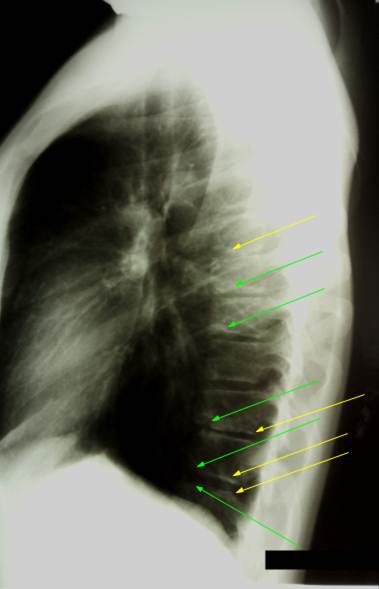

Боковая

рентгенограмма позвоночника ребенка 13 лет, на ней видна развернутая картина

поражения грудного отдела юношеским остеохондрозом. Наблюдаются хрящевые узлы,

вдающиеся в тела позвонков (обозначены зелеными стрелками), явления склероза

замыкательных пластинок вокруг узлов, а также фрагментарность и разорванность

апофизарных колец (желтые стрелки). Межпозвоночные пространства неравномерной

высоты, что свидетельствует о изменениях

в межпозвоночных дисках.